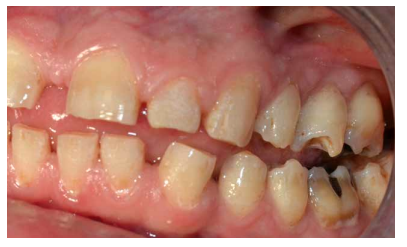

En la bibliografía se describe con detalle los defectos del esmalte que presentan los pacientes diagnosticados del síndrome de Morquio. Estos defectos son una característica aparentemente constante en la enfermedad y, por lo tanto, hace necesaria las visitas al odontólogo para su control evitándose problemas mayores. Dichos defectos consisten en un esmalte anormalmente delgado, que es áspero debido a los numerosos hoyos diminutos y a una superficie irregular. La delgadez del esmalte da como resultado una forma alterada y decoloración de los dientes que, añadido a los diastemas interdentales, provocan alteraciones en la oclusión. Aparte de estos defectos, el esmalte es histológicamente normal y tiene una dureza y radiodensidad normales. El tratamiento odontológico de los pacientes con MPS-IV requiere colaboración multidisciplinar, debido a que las manifestaciones orales de la enfermedad pueden aparecer a cualquier edad, resultando en ocasiones tedioso para el paciente y complicado para el profesional. Especial mención merecen las terapias utilizadas como tratamiento sintomático de la enfermedad, así como el manejo de la vía aérea en el caso de intervenciones bajo anestesia general o sedación para tratar ciertas patologías del territorio bucomaxilodental.

The enamel defects presented by patients diagnosed with Morquio syndrome are described in detail in the bibliography. These defects are an apparently constant feature in the disease and, therefore, make visits to the dentist necessary for their control, avoiding major problems. These defects consist of an abnormally thin enamel that is rough due to numerous tiny holes and an irregular surface. The thinness of the enamel results in an altered form and discoloration of the teeth, which added to the interdental diastemas, cause alterations in the occlusion. Apart from these defects, the enamel is histologically normal and has a normal hardness and radiodensity.

Dental treatment of patients with MPS-IV requires multidisciplinary collaboration, because the oral manifestations of the disease can appear at any age, being sometimes tedious for the patient and complicated for the professional. Special mention should be made of the therapies used as a symptomatic treatment of the disease, as well as the management of the airway in the case of interventions under general anesthesia or sedation to treat certain pathologies of the bucomaxillodental territory.